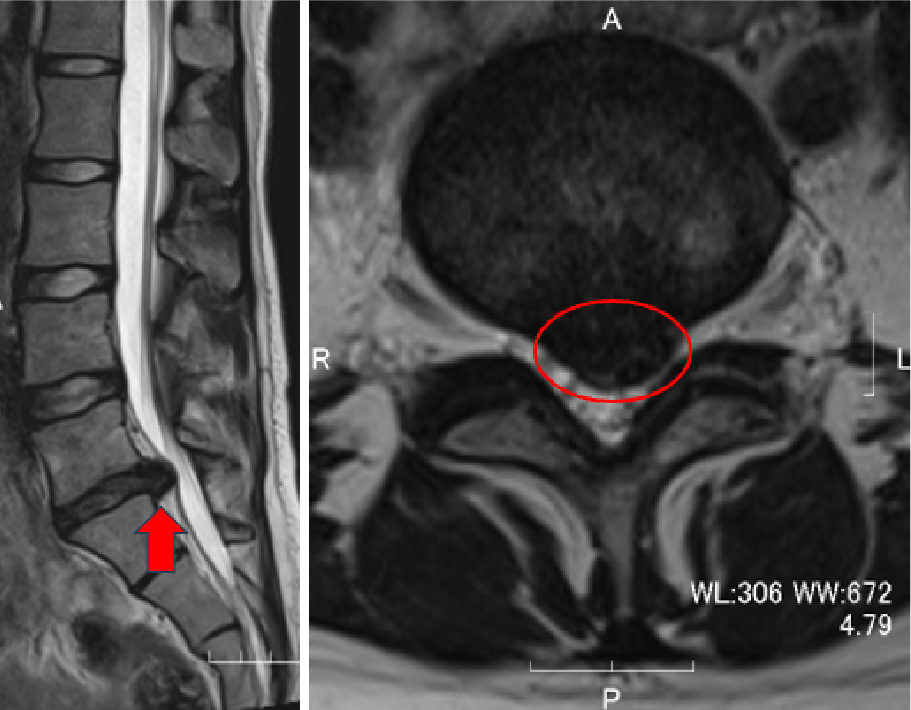

術前MRI:大きなヘルニア

(左図の矢印、右図の丸印)

を認め神経を強く圧迫しています